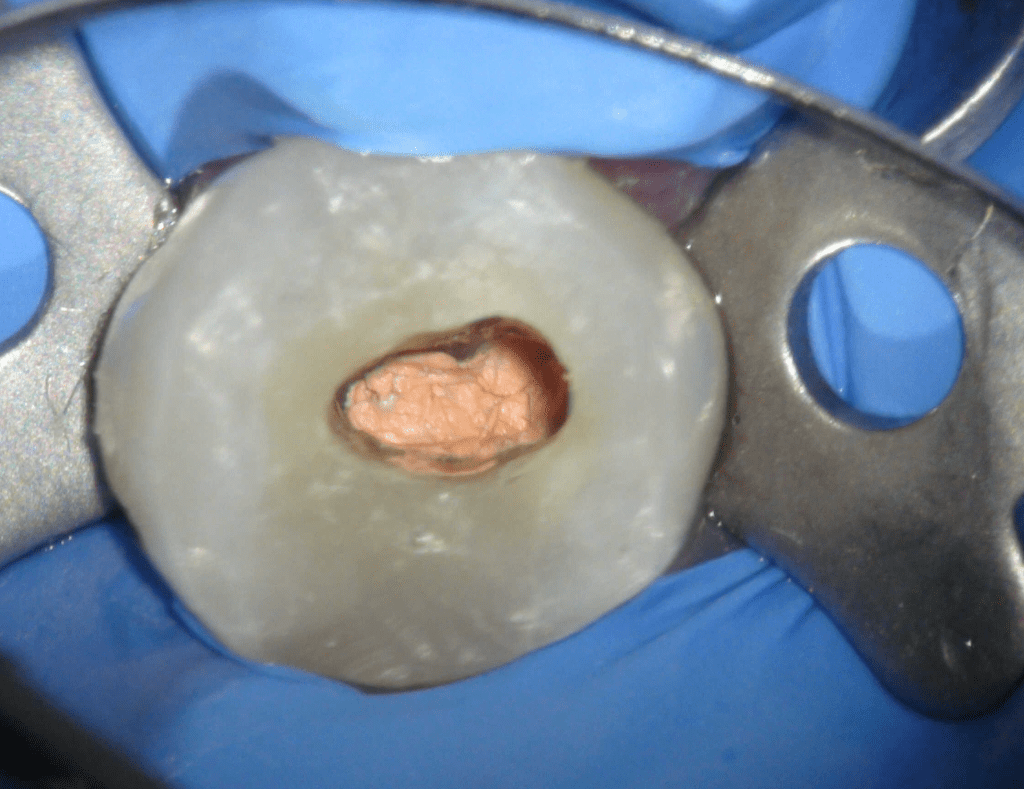

Pulpotomía biodentine + reco preendio